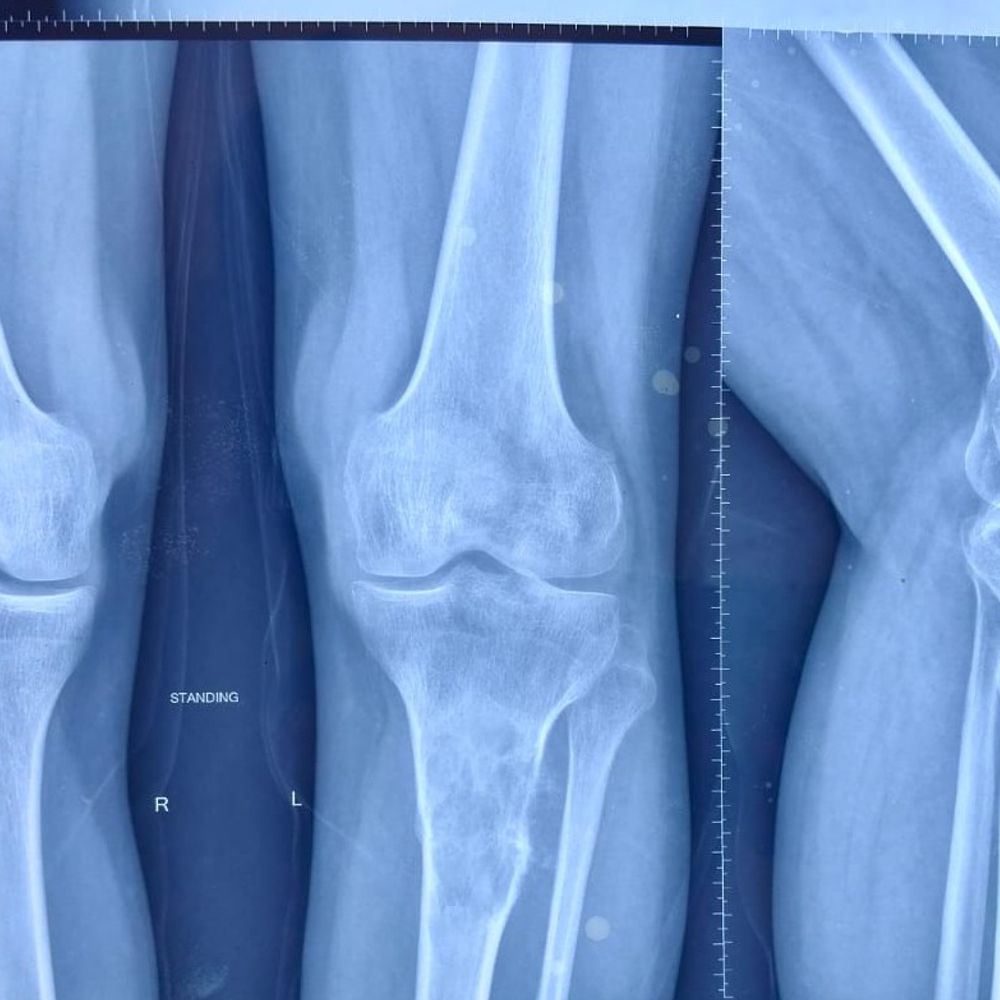

पटना एम्स के डॉक्टरों ने 25 वर्षीय युवक का पैर दुर्लभ ईविंग सारकोमा कैंसर से बचाया है। आमतौर पर इस प्रकार के कैंसर में अंग विच्छेदन (अम्प्यूटेशन) की आवश्यकता होती है, लेकिन विशेषज्ञों ने 'लिंब सेवेज' तकनीक का सफलतापूर्वक उपयोग किया। उत्तर प्रदेश के देवरिया निवासी मकर ध्वज कुछ महीने पहले असहनीय दर्द से पीड़ित थे। उनके बाएं पैर में एक मामूली चोट के बाद दर्द शुरू हुआ, जो धीरे-धीरे बढ़ता गया। शुरुआत में इसे सामान्य फ्रैक्चर माना गया था, लेकिन उनकी स्थिति लगातार बिगड़ती गई। 13 मई 2025 को मकर ध्वज एम्स पहुंचे 13 मई 2025 को मकर ध्वज एम्स पटना पहुंचे। यहां जांच रिपोर्ट में खुलासा हुआ कि यह सामान्य फ्रैक्चर नहीं, बल्कि 'पैथोलॉजिकल फ्रैक्चर' था, जो किसी गंभीर बीमारी का संकेत होता है। विस्तृत जांच के बाद उन्हें ईविंग सारकोमा नामक दुर्लभ और आक्रामक बोन कैंसर होने की पुष्टि हुई। यह एक ऐसी गंभीर स्थिति थी, जिसमें अक्सर मरीज को अपना अंग गंवाना पड़ता है। हालांकि, एम्स पटना के ऑर्थोपेडिक्स, रेडिएशन ऑन्कोलॉजी और सर्जिकल ऑन्कोलॉजी विभागों के विशेषज्ञों ने मिलकर एक महत्वपूर्ण निर्णय लिया। उन्होंने अंग विच्छेदन (अम्प्यूटेशन) के बजाय 'लिंब सेवेज' तकनीक का उपयोग कर अंग को बचाने का प्रयास करने का फैसला किया। करीब 6-7 महीने मरीज को कीमोथेरेपी दी इलाज की प्रक्रिया चुनौतीपूर्ण रही। अगस्त 2025 से जनवरी 2026 तक मकर ध्वज को कीमोथेरेपी दी गई। इस उपचार के परिणामस्वरूप ट्यूमर का आकार धीरे-धीरे कम हो गया, जिससे सर्जरी संभव हो सकी। चिकित्सकों की इस सफल पहल ने युवक को नया जीवन प्रदान किया है। ऑपरेशन थिएटर में डॉक्टरों की टीम ने एक बेहद जटिल और अत्याधुनिक सर्जरी को अंजाम दिया। कैंसर से प्रभावित टिबिया के हिस्से को सावधानीपूर्वक शरीर से अलग किया गया। इसके बाद हड्डी को बाहर निकालकर 50 Gy की उच्च डोज रेडिएशन दी गई, ताकि उसमें मौजूद कैंसर कोशिकाएं पूरी तरह समाप्त हो जाएं। सबसे खास बात यह रही कि उसी हड्डी को दोबारा शरीर में प्रत्यारोपित किया गया। मजबूती के लिए टाइटेनियम प्लेट और स्क्रू लगाए गए, जबकि मसल फ्लैप तकनीक के जरिए उस हिस्से की संरचना और कार्यक्षमता को फिर से विकसित किया गया। यह पूरी प्रक्रिया तकनीकी रूप से बेहद जटिल थी, लेकिन डॉक्टरों की टीम ने इसे सटीकता के साथ सफलतापूर्वक पूरा किया। सर्जरी के बाद मकर ध्वज की रिकवरी भी उतनी ही प्रेरणादायक रही। दूसरे ही दिन से उनकी फिजियोथेरेपी शुरू कर दी गई। तीन सप्ताह के भीतर उनकी स्थिति स्थिर हो गई और उन्हें अस्पताल से छुट्टी मिल गई। अब वे सहारे के साथ चल पा रहे हैं और धीरे-धीरे सामान्य जीवन की ओर लौट रहे हैं। डॉक्टरों के मुताबिक, यह सफलता सिर्फ एक ऑपरेशन की नहीं बल्कि टीमवर्क, सही समय पर इलाज और आधुनिक तकनीक के समन्वय का परिणाम है। ऑपरेशन में 11 सदस्यीय टीम रही शामिल सर्जिकल ऑन्कोलॉजी विभाग के प्रमुख डॉ. जगजीत कुमार पांडेय ने बताया कि अब चिकित्सा विज्ञान इतनी प्रगति कर चुका है कि कई मामलों में अंग को बचाना संभव हो गया है, बशर्ते समय पर सही निर्णय लिया जाए। इस जटिल ऑपरेशन को सफल बनाने में डॉ. प्रवीण, डॉ. एफ्रेम, डॉ. अज़हर, डॉ. प्रितांजलि, डॉ. निलेश और डॉ. हरिकेश की अहम भूमिका रही। साथ ही एनेस्थीसिया विभाग का योगदान भी बेहद महत्वपूर्ण रहा, जिसकी वजह से पूरी प्रक्रिया सुरक्षित और सुचारू ढंग से पूरी हो सकी। 13 मार्च 2026 को मकरध्वज का पटना AIIMS में सफल ऑपरेशन किया गया। इस दौरान 26 दिनों तक पेशेंट को अस्पताल में अंडर ऑब्जर्वेशन में रखा गया। पटना AIIMS में ईविंग सारकोमा कैंसर सफल ऑपरेशन का पहला केस हैं, जिसे AIIMS के डॉक्टरों ने कर, नया कीर्तिमान स्थापित किया है। फिलहाल पेशेंट पूरी तरह स्वस्थ हैं और कल यानी मंगलवार को पटना AIIMS से डिस्चार्ज कर दिया गया है।